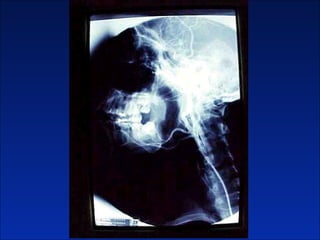

Queratoquiste odontogenico

Reseccion quirurgica de queratoquiste odontogenico

Cuatro años después

Otro caso